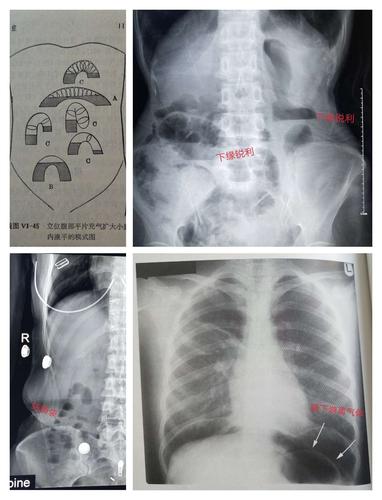

梗阻发生后的4~6小时,腹平片上即可见胀气的肠袢及多数气液平面.

肠梗阻的征象为腹部三个及以上高低不等呈阶梯状排列的气液平

急诊卧位及立位腹平片正常气腹小肠梗阻前哨肠曲

腹部一长液气平面